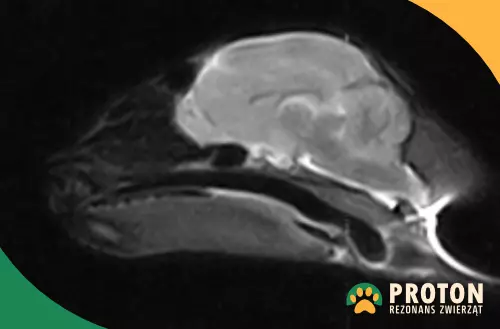

Obraz RM głowy psa

Rezonans głowy psa